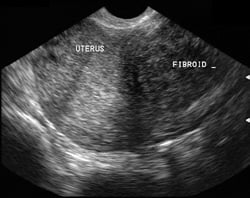

Son 20 yıldır yaygın şekilde kullanılan ultrasonografi myomlardaki en önemli tanı aracıdır. Yumurtalıklara yakın bulunan myom nüveleri over tümörleri ile karıştırılabilir.